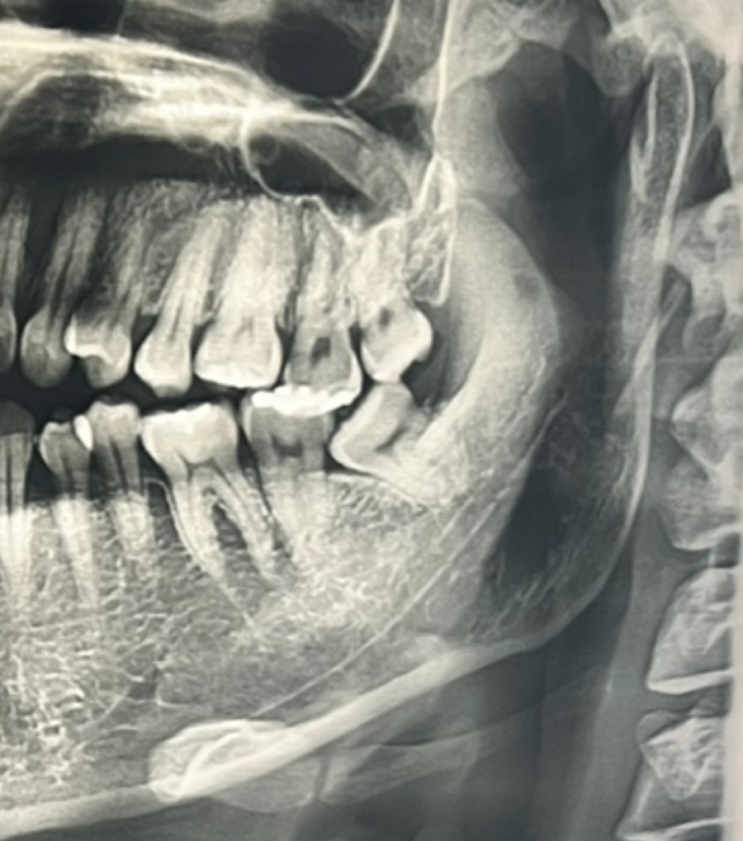

울산 바로치과 사랑니 위, 아래 발치 후기(실비청구)

안녕하세요 뉴딘딘입니다 :D 오늘은 미루고 미뤘던 사랑니를 뽑고 왔어요.. 아직 울산에 정착한 치과가 없...